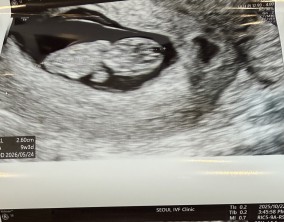

기대보다 먼저 찾아온 선물 같은 순간

이경훈 원장님께서 친절하고 꼼꼼하게 신경 써 주셨고, 간호사 분들께서도 하나하나 자세히 설명해 주시며 공감해 주셔서 치료 과정이 훨씬 편안하게 느껴졌습니다. 의료진 모두…